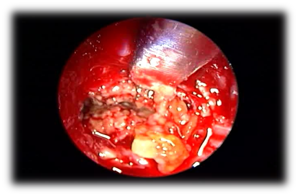

Allergic Fungal Rhinosinusitis AFS: Allergic fungal sinusitis is a non-invasive fungal sinusitis occurs in immunocompetent individuals in whom there is a strong inflammatory response to the fungal infection. This commonly results in a thick mucin that can be expansile and cause bony decalcification. There is also marked mucosal thickening and bone resorption due to the secretion of enzymes. Endoscopic examinations of these patients show the presence of allergic mucin and polyps. Major criteria for diagnosis by Bent and Kuhn their diagnostic criteria depend on the histologic, radiographic, and immunologic characteristics of the disease which include type 1 hypersensitivity, the presence of nasal polyposis, characteristic CT findings of heterogeneous hyperdensities that are often unilateral and asymmetric (Figure 3), an eosinophilic mucin and positive fungal stain or culture.16 AFS in sphenoid sinus can easily compress the cranial nerves. It was reported that cranial neuropathies develop in 10% of the sphenoid AFS with bone erosion. Treatment involves endoscopic sphenoidotomy to clear polyps and allergic mucin (Figure 4), and to restore the ventilation and drainage of sinuses with combination of medical therapy with corticosteroids. Anti-fungal treatment is usually not required. Histopathology is important to be obtained for the specimen which shows allergic mucin containing fungal components without any tissue invasion. These patients may get benefit from Immunotherapy post-op.

Figure 4 Mud and mucin in isolated sphenoid allergic fungal sinusitis.